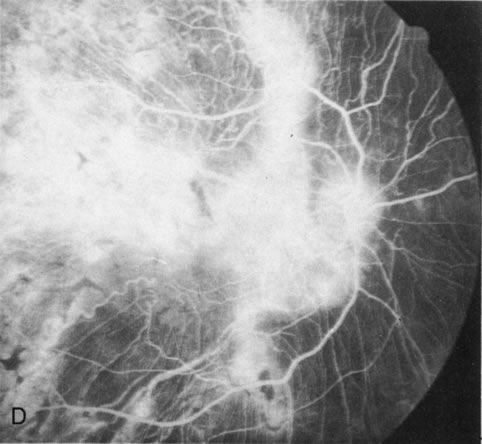

Generalized choroidal dystrophy is usually noted in middle-aged mildly symptomatic individuals who show a predominantly peripapillary or pericentral distribution of choroidal atrophy. Gradually, over the years these areas enlarge to eventually involve the entire retina. These changes are vividly seen on FA (Fig. 6).

Fig. 6. Generalized choroidal dystrophy. This 65-year-old woman gradually developed enlarging, progressive areas of choroidal atrophy over a 20-year period. When initially seen, the abnormalities were confined to the peripapillary and macular region (A,B). In a recent examination, the generalized choroidal atrophy is vividly demonstrated on angiography (C–F).